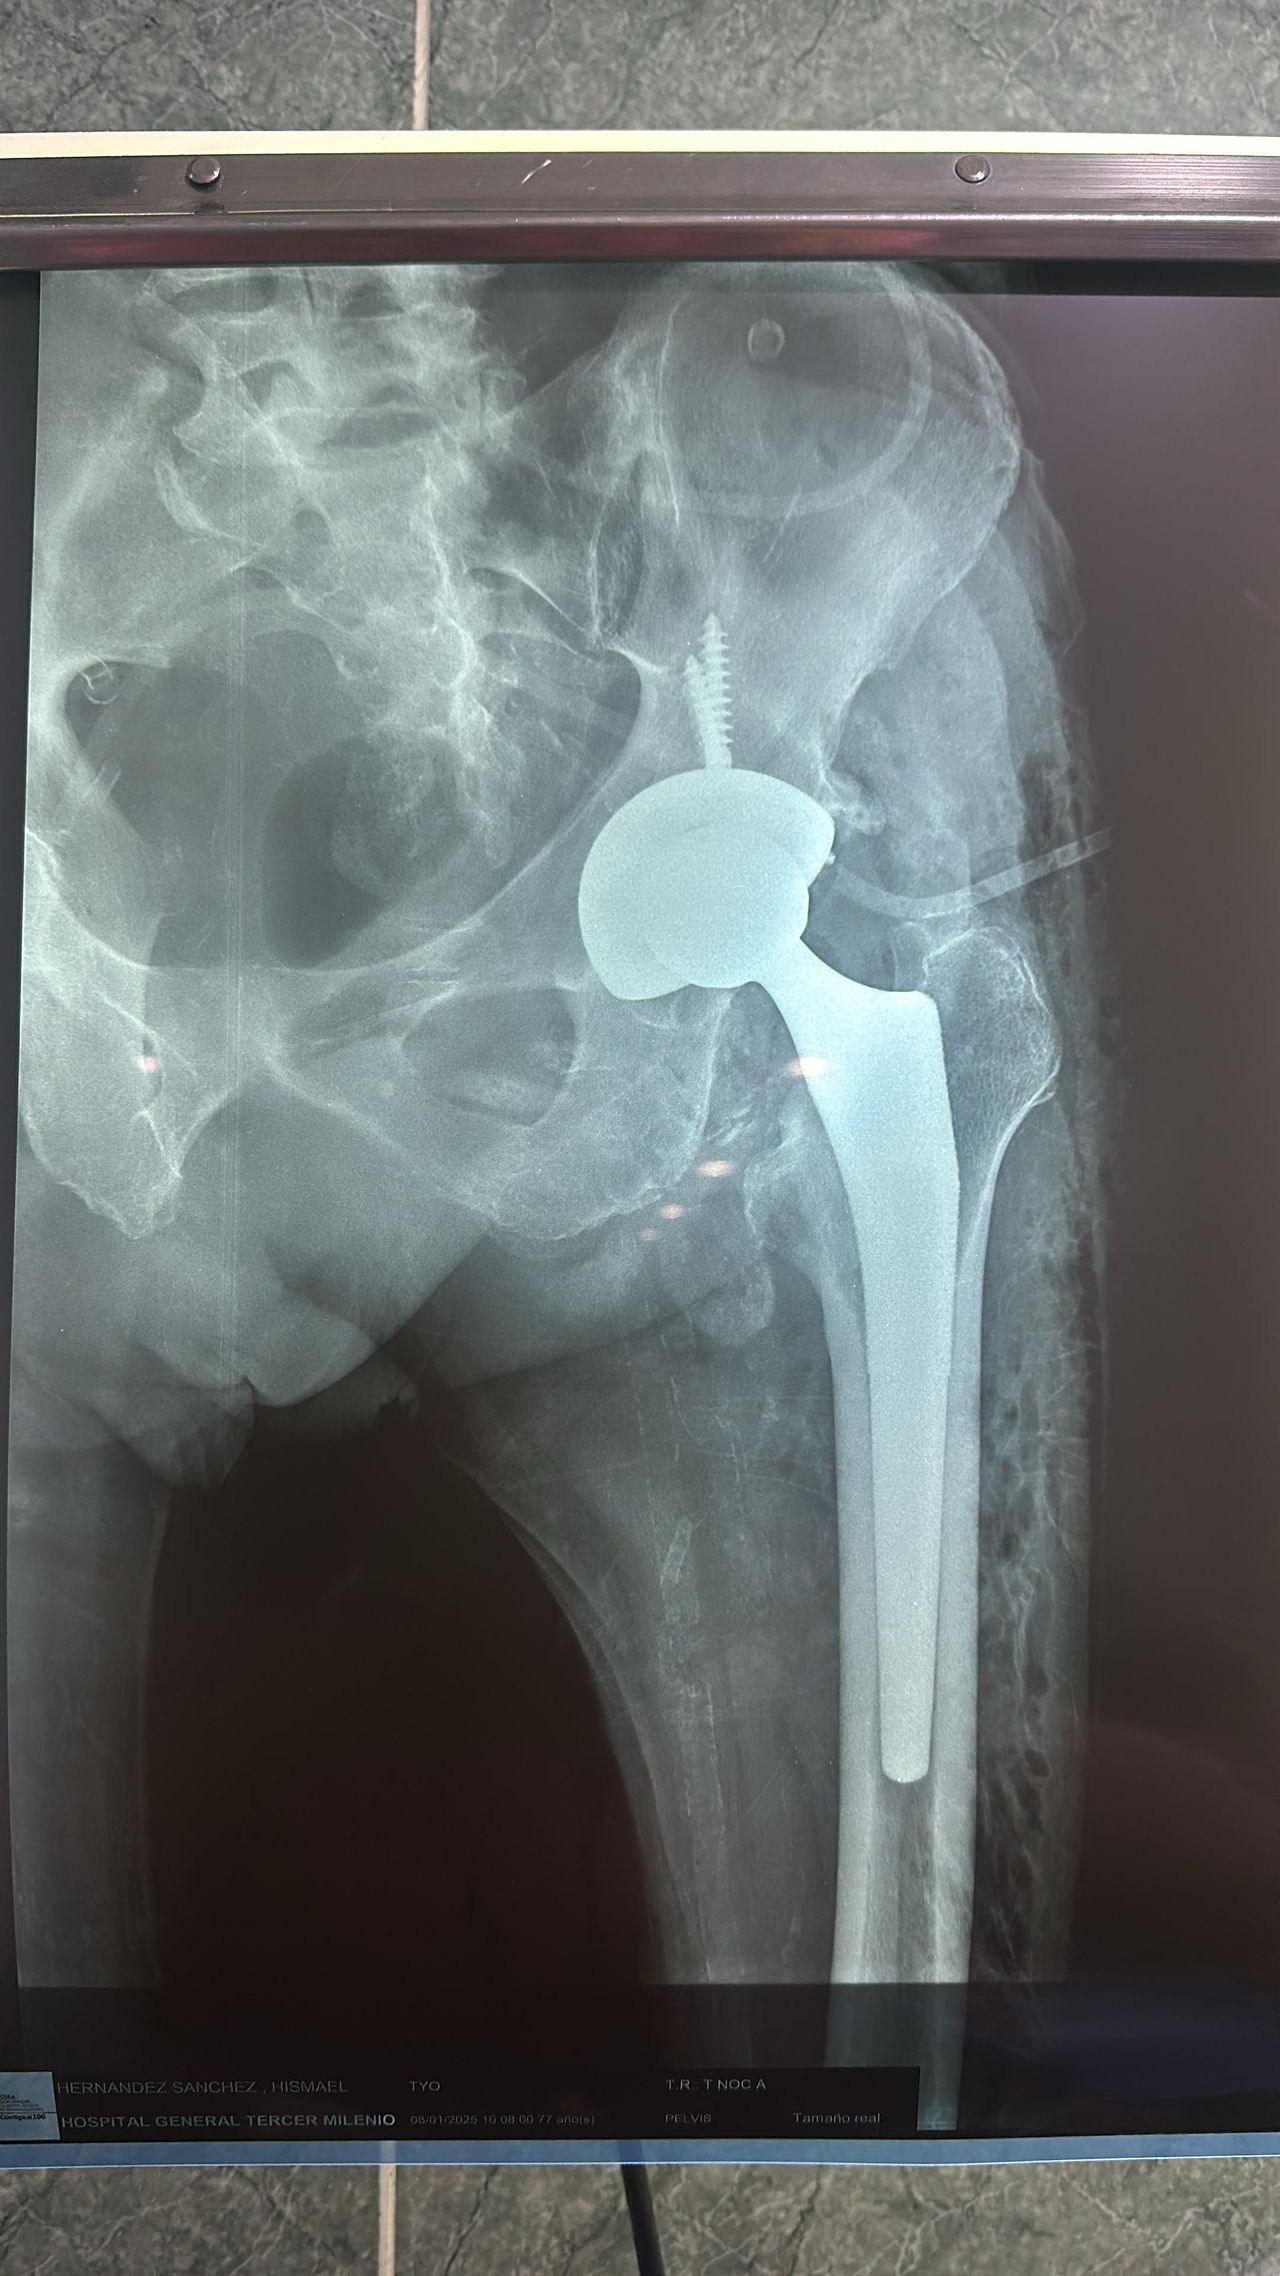

• Reemplazo articular de cadera

• Artroplastia rodilla con prótesis total